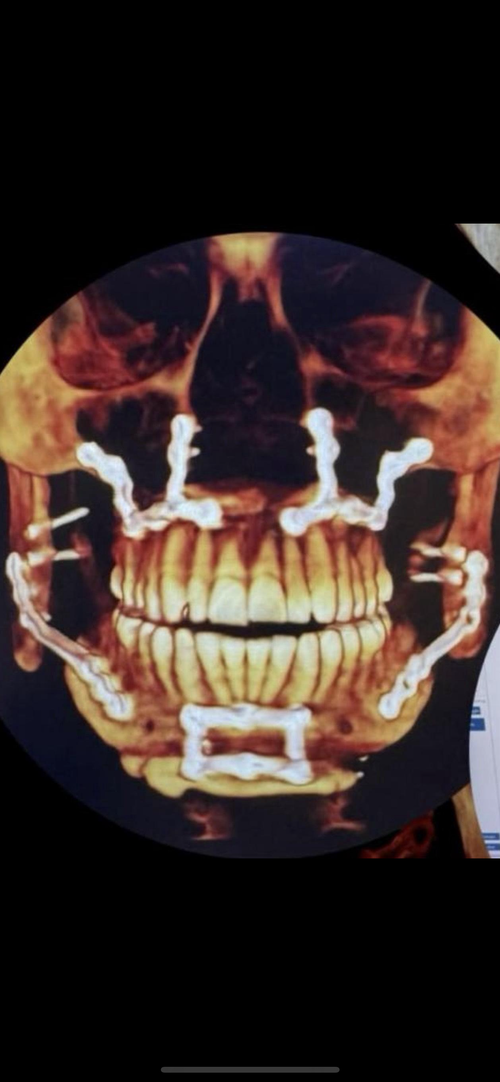

I had my consultation over my CT scan today and basically he told me I had to do orthodontic decompensation in order to do the surgery.

I had my consultation over my CT scan today and basically he told me I had to do orthodontic decompensation in order to do the surgery.